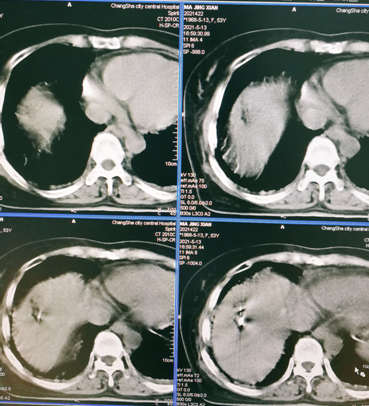

肿瘤消融术

3.消融术在实体肿瘤治疗的应用范围广--肝、肺、肾及肾上腺、骨与软组织、乳腺、甲状腺等。